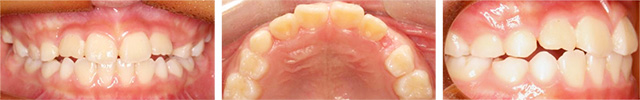

위, 아래 앞니가 거꾸로 물리는 반대교합으로 정밀진단 결과 3급 부정교합 환자 입니다. 반대교합의 경우 오랫동안 방치하게 되면 아래턱뼈의 성장이 촉진되어 시간이 흐를수록 점점 길어지기 때문에 초기에 교정하는 것이 중요합니다. 고운미소에서는 가철식 교정장치를 이용하여 앞니를 전방으로 경사이동 시키는 교정을 진행하였습니다.